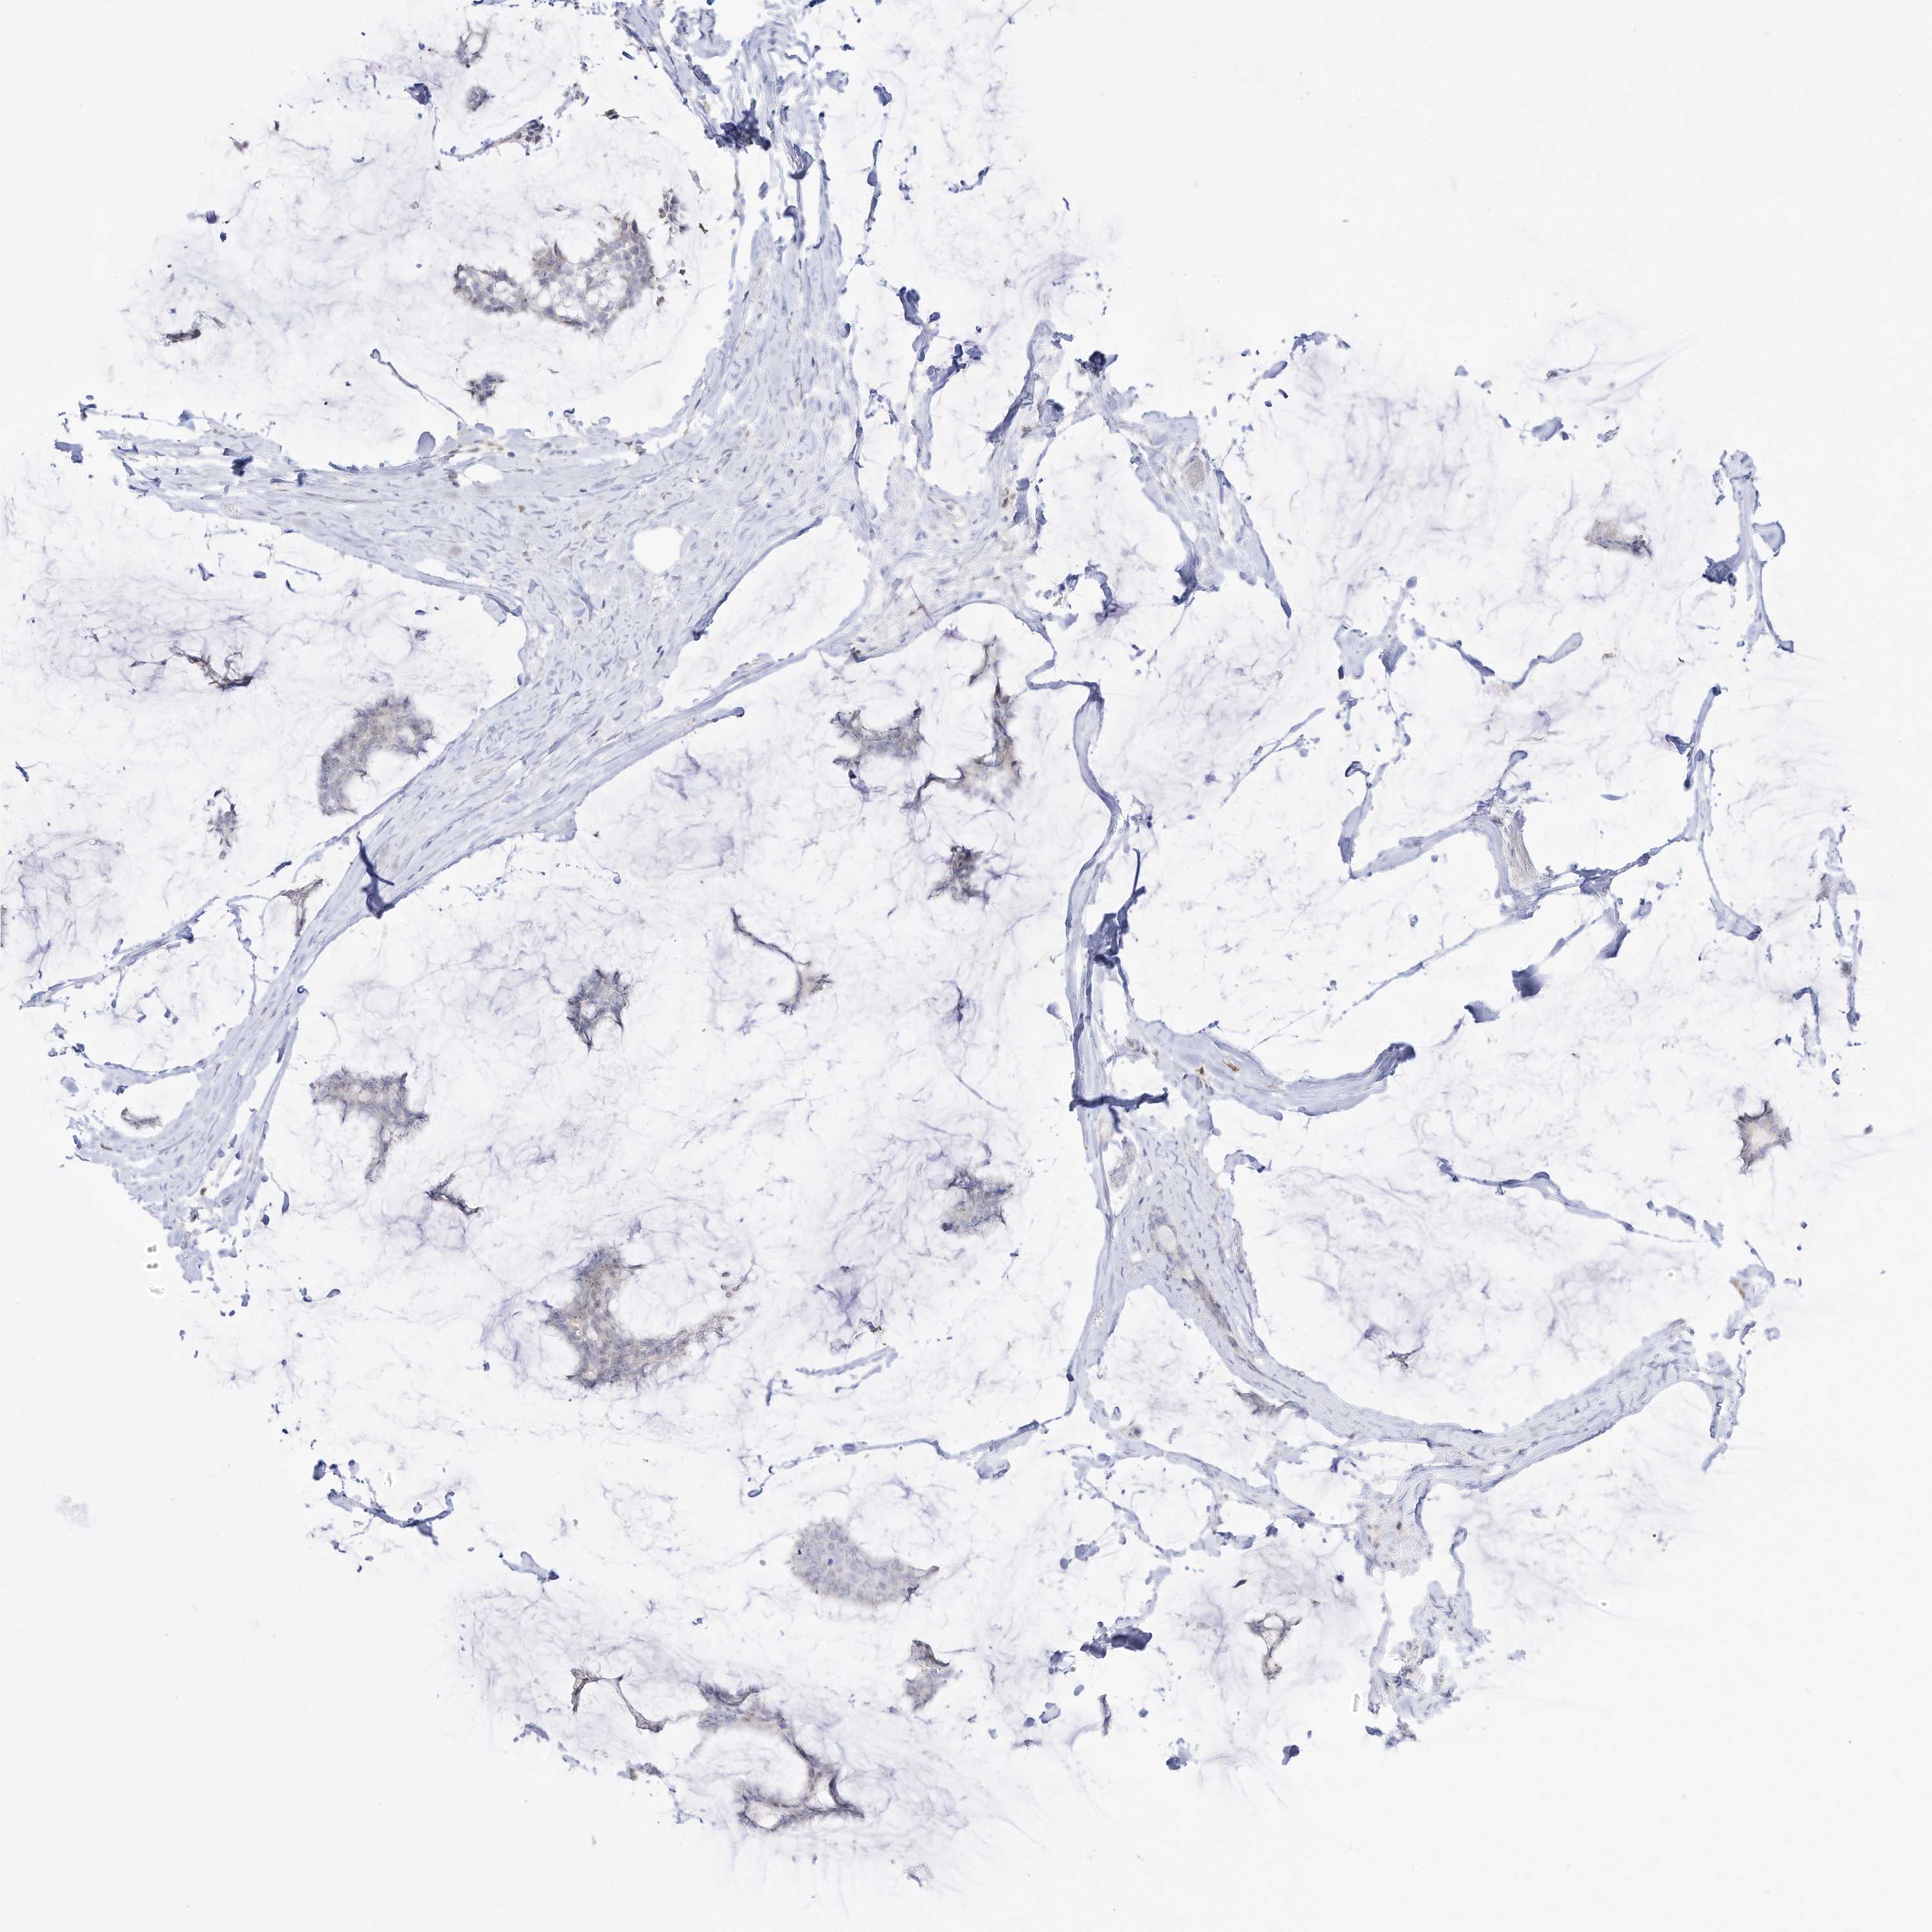

BRCA TCGA BRCA VALIDATION PROTEIN EXPRESSION

ANTIBODIES

AND

VALIDATION